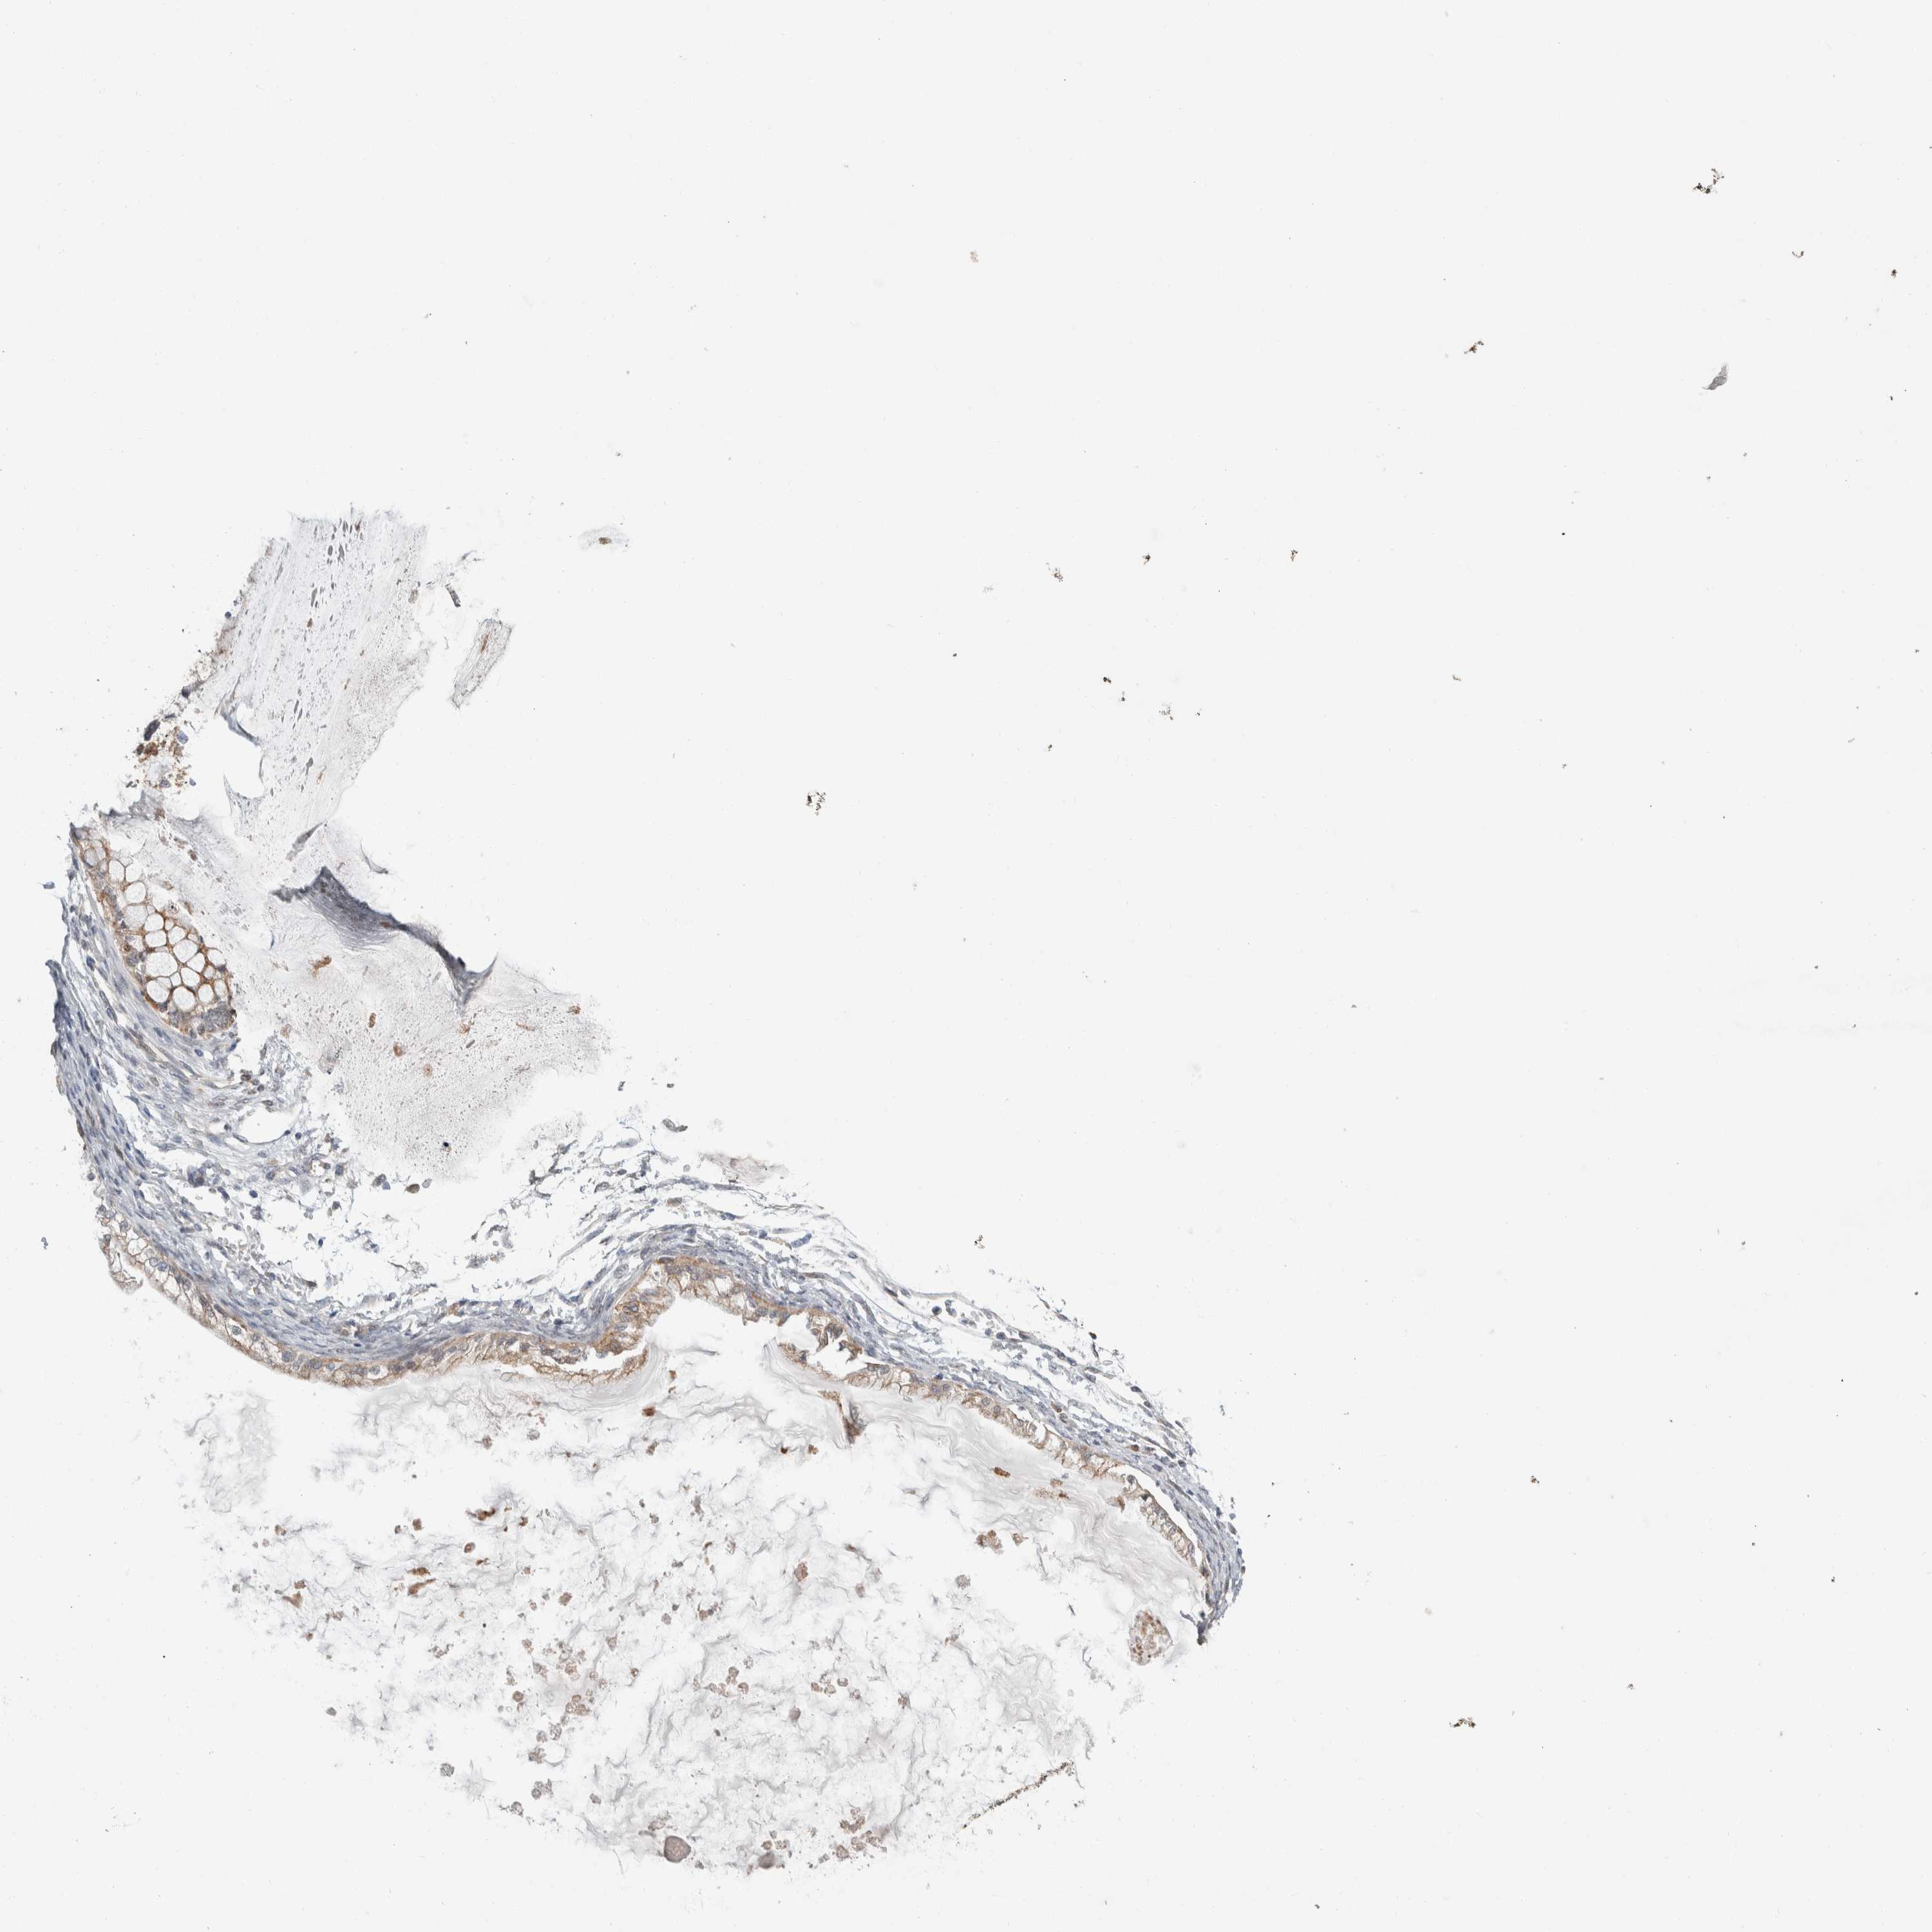

OVARIAN CANCER - Protein expressioni

A mouse-over function shows sample information and annotation data. Click on an image to view it in a full screen mode. Samples can be filtered based on level of antibody staining by selecting one or several of the following categories: high, medium, low and not detected. The assay and annotation is described here.

Note that samples used for immunohistochemistry by the Human Protein Atlas do not correspond to samples in the TCGA dataset.

Antibody stainingi

Antibody staining in the annotated cell types in the current human tissue is reported as not detected, low, medium, or high, based on conventional immunohistochemistry profiling in selected tissues. This score is based on the combination of the staining intensity and fraction of stained cells.

Each image is clickable and will lead to virtual microscopy that enables deeper exploration of all samples and also displays staining intensity scores, fraction scores and subcellular localization as well as patient and tissue information for each sample.

Antibody HPA024361

Antibody HPA064939

Cystadenocarcinoma, serous, NOS

Carcinoma, endometroid

Cystadenocarcinoma, mucinous, NOS

Carcinoma, NOS